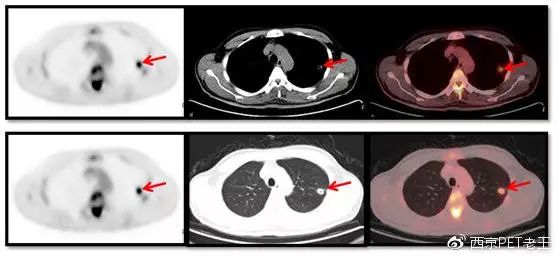

我们又发现了这么多的骨转移病变,那原发病灶究竟在哪里呢?我们仔细寻找,在左肺上叶发现了一个空洞样病变,边缘见细毛刺及胸膜牵拉征,呈葡萄糖代谢异常增高,我们考虑为恶性病变(肺癌?),如下图:

左肺上叶发现了一个空洞样病变(红色)

我们给出的结论:左肺上叶肺癌伴肝脏、骨广泛性转移。

如何验证我们的诊断?肺内的病变比较小,有空洞,位置也不好穿刺,临床选择了肝脏病变穿刺,病理结果如下: